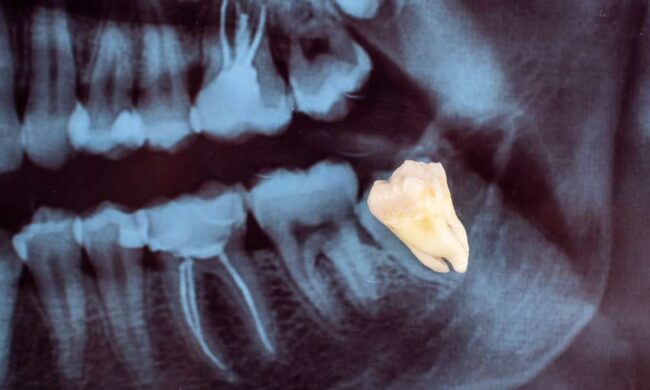

Bone grafting is a crucial procedure in modern dentistry, particularly for patients considering dental implants. It plays a vital role in restoring oral health and ensuring the long-term success of dental treatments. At Pristine Oral & Maxillofacial Surgery, led by Dr. Garry Shnayder, we specialize in advanced bone grafting techniques that support both dental implants…